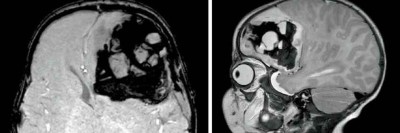

Drohende fatale Blutung nach Knopfzelleningestion – weltweit einmalige Op.

Ein kleines Mädchen verschluckt eine Knopfzelle. Als die Extraktion drei Stunden später gelingt, ist der Ösophagus bereits stark verätzt. Fistelgänge bilden sich, deren Durchbruch zur Karotis am übernächsten Tag kurz bevorzustehen scheint. Weltweit erstmalig in einem solchen Setting entscheidet sich das Team zur präventiven Operation.

Bauchhoden/© Springer Medizin Verlag GmbH, Blutung im transversalen als auch im saggitalen Schnitt/© Institut für Diagnostische und Interventionelle Radiologie der Uniklinik Köln; mit freundlicher Genehmigung, Abdomensonographie: 14,7 mm große zystische Struktur im Bereich des rechten Ovars/© Isaev Y et al. / all rights reserved Springer Medizin Verlag GmbH, Röntgen einer Beckenfraktur und Abdomen-CT bei Jugendlichem/© Karvouniaris N. et al. / all rights reserved Springer Medizin Verlag GmbH, Drohende ösophago-arterielle Fistel nach Batterieingestion/© Lohmann J et al. doi.org/10.1007/s00101-024-01477-3 unter CC-BY 4.0, Kleinkind und Teddy mit Verband/© simoningate / Getty Images / iStock (Symbolbild mit Fotomodell), Akute Appendizitis/© Springer Medizin, Kind mit Gipsarm/© nycshooter / Getty Images / iStock (Symbolbild mit Fotomodell), Appendizitis /© Springer Medizin Verlag GmbH, Operationstechnik der Limberg-Plastik bei Sinus pilonidalis/© Jamal Driouch et al., Ärztin und Patientin im Gespräch/© andrei_r / Getty Images / iStock (Symbolbild mit Fotomodell), Bunte Plastikperlen/© Steven White / Getty Images / iStock, Ärztin betrachtet Röntgenbild/© dusanpetkovic1 / stock.adobe.com (Symbolbild mit Fotomodell), Search Icon, Knochensäge im Einsatz bei Knie-TEP/© Issara / stock.adobe.com (Symbolbild mit Fotomodellen), Hirntumoren sichtbar im MRT/© semnic / Getty Images / iStock (Symbolbild mit Fotomodell), Lungentrainer/© S@photo / stock.adobe.com (Symbolbild mit Fotomodell)